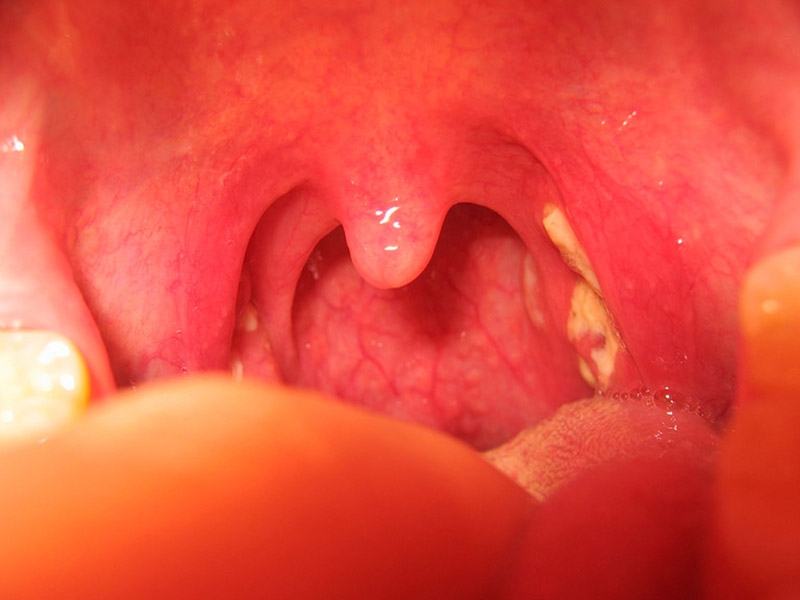

Viêm họng hạt có mủ là tình trạng nguy hiểm, dễ dẫn đến nhiều biến chứng khôn lường. Ở bài viết này, chúng ta cùng tìm hiểu nguyên nhân và cách chữa viêm họng hạt có mủ hiệu quả.

Có thể nói rằng, viêm họng hạt có mủ là biểu hiện nghiêm trọng của bệnh viêm họng. Tình trạng này không chỉ gây đau đớn và khó chịu cho bệnh nhân, mà còn dễ dẫn đến nhiều biến chứng nguy hiểm, thậm chí là tiền đề dẫn đến ung thư vòm họng. Vì thế, việc chủ động tìm hiểu nguyên nhân và cách chữa viêm họng hạt có mủ là điều vô cùng cần thiết.

Viêm họng hạt có mủ thường đi kèm với các dấu hiệu và triệu chứng sau: